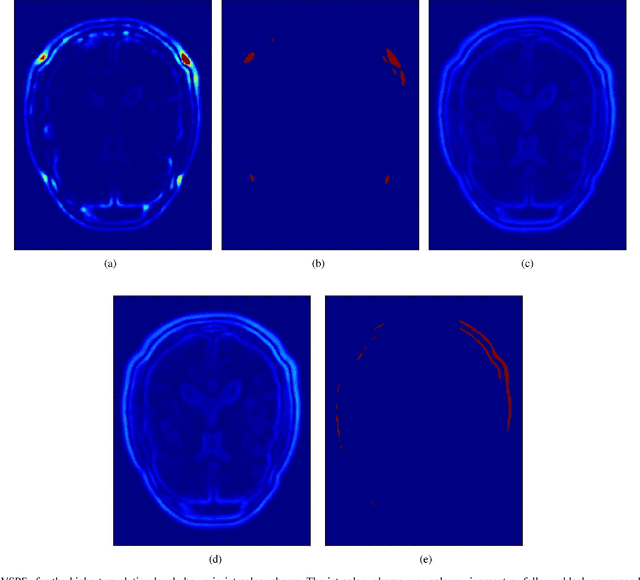

This paper presents a novel probabilistic voxel selection strategy for medical image registration in time-sensitive contexts, where the goal is aggressive voxel sampling (e.g. using less than 1% of the total number) while maintaining registration accuracy and low failure rate. We develop a Bayesian framework whereby, first, a voxel sampling probability field (VSPF) is built based on the uncertainty on the transformation parameters. We then describe a practical, multi-scale registration algorithm, where, at each optimization iteration, different voxel subsets are sampled based on the VSPF. The approach maximizes accuracy without committing to a particular fixed subset of voxels. The probabilistic sampling scheme developed is shown to manage the tradeoff between the robustness of traditional random voxel selection (by permitting more exploration) and the accuracy of fixed voxel selection (by permitting a greater proportion of informative voxels).